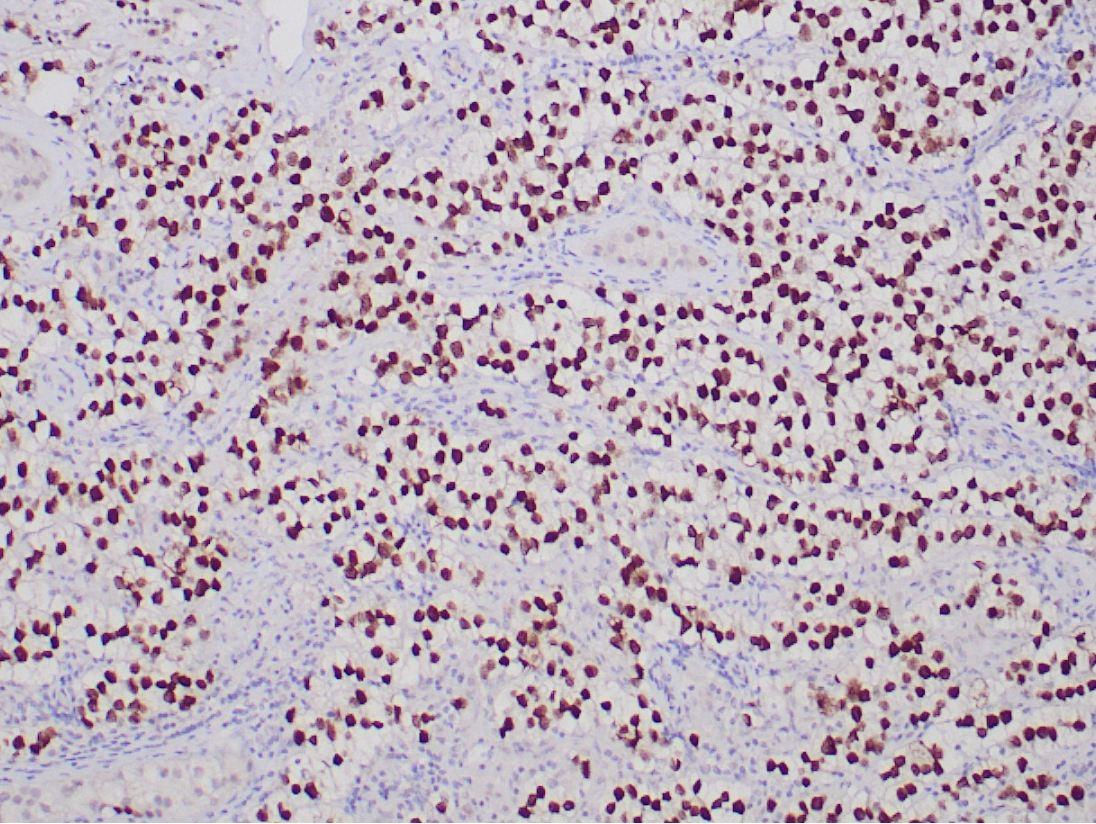

SALL4 (PL-24)

BOYANMASI GEREKEN ALAN : Çekirdek

POZİTİF KONTROL : Seminom